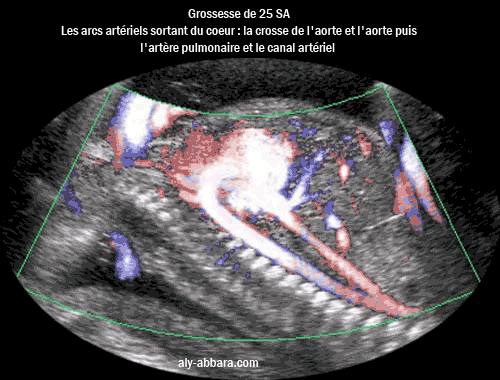

Echographie associée au Doppler Dynamic Flow montrant le cur ftal à 25 SA :

les deux arcs artériels partant du cur, c'est-à-dire l'arc aortique avec sa crosse et

l'arc

pulmonaire

avec son canal artériel communicant avec l'aorte